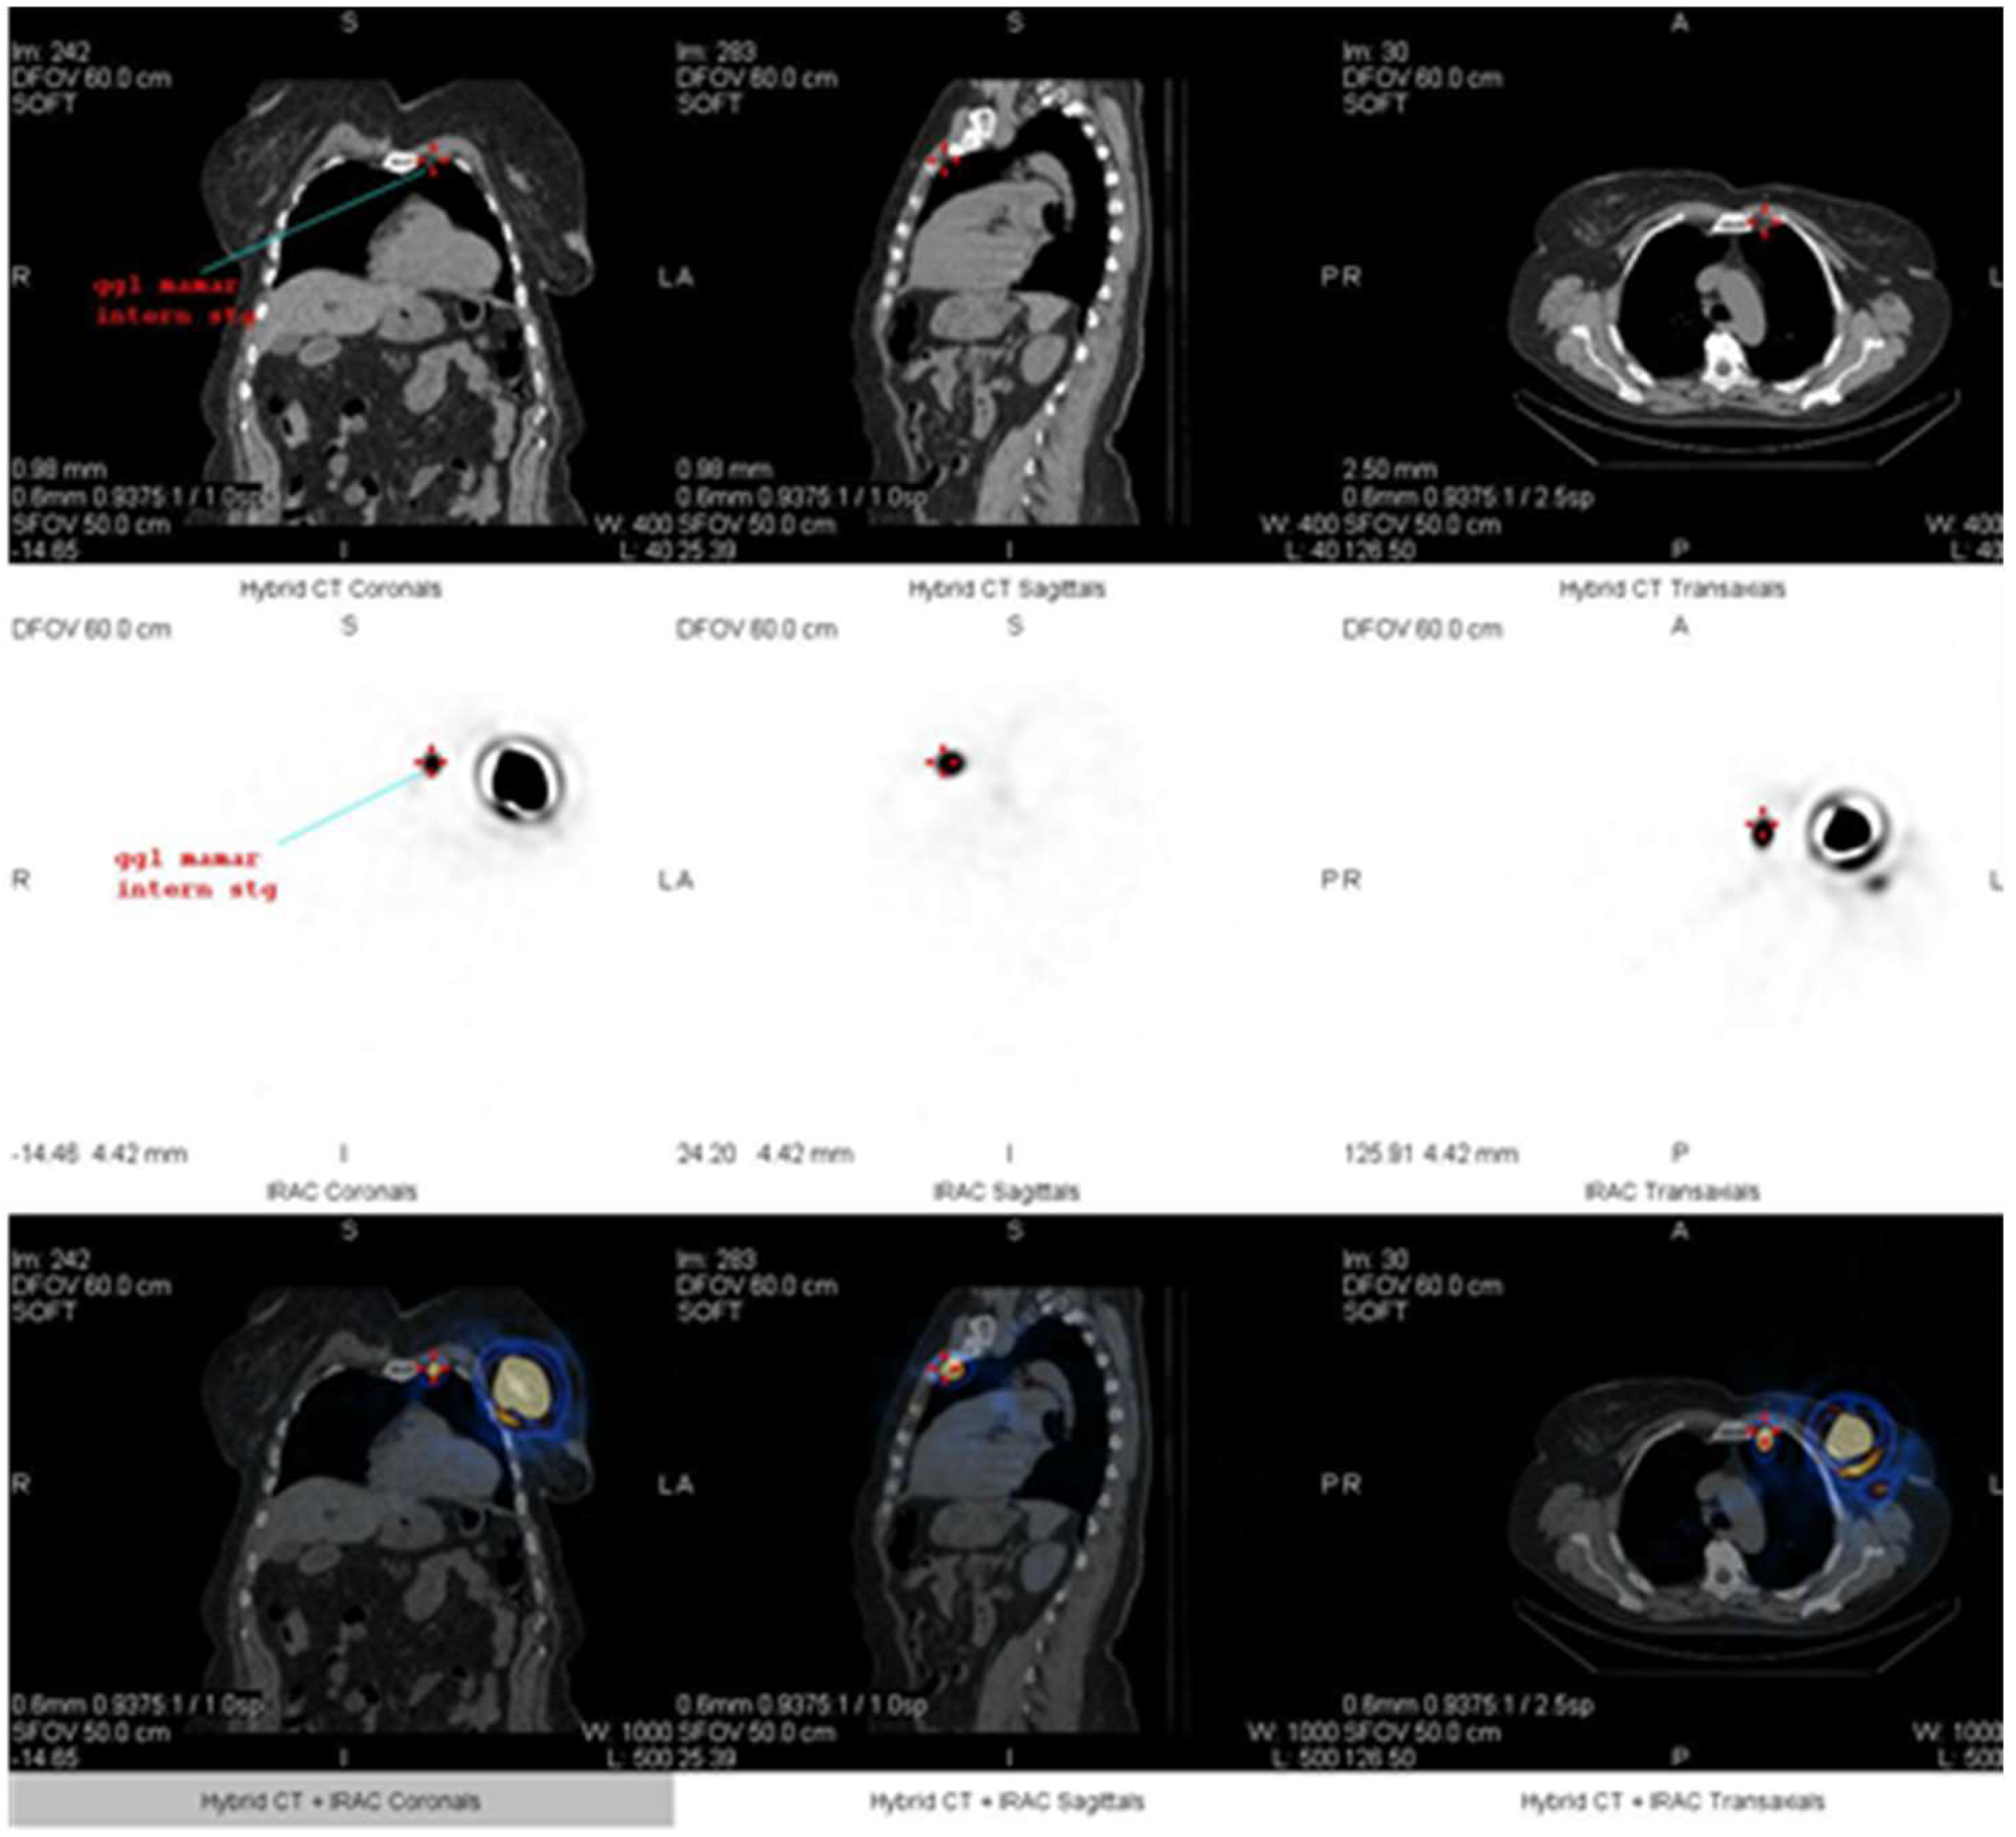

2. Case Report